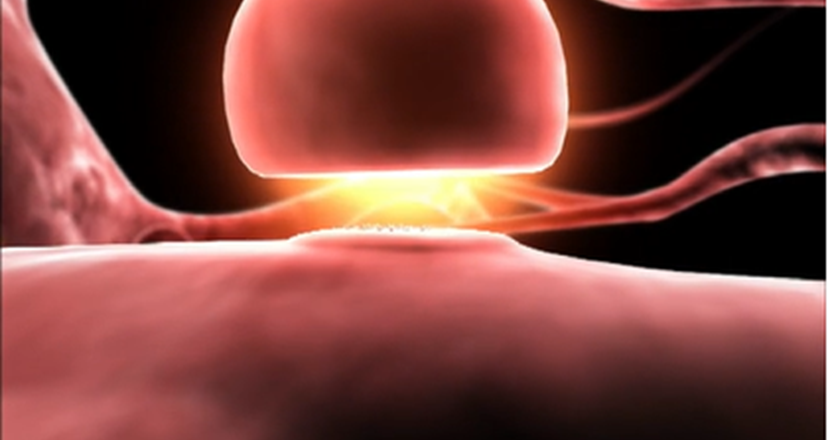

Parkinsonföreläsning

Den 7 april 2022 hade riksorganisationen en föreläsning om Parkinson. Nu kan du se den i efterhand, inspelad och textad.